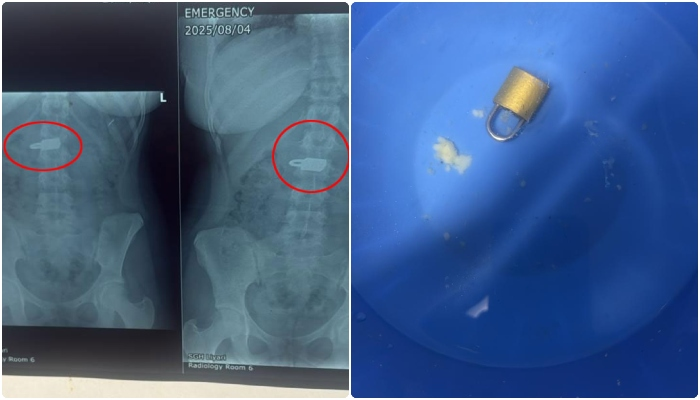

کراچی (ہیلتھ ڈیسک): کراچی کے لیاری جنرل اسپتال میں ملیر کھوکھرا پار کی رہائشی خاتون کے پیٹ میں موجود تالہ سرجری کے بغیر نکال لیا گیا۔سربراہ لیاری جنرل اسپتال ڈاکٹر انجم رحمان کا کہنا تھا کہ ملیر کھوکھرا پار کی رہائشی 23 سالہ خاتون ذہنی طور پر مفلوج ہیں اور انہوں نے لوہے کا تالا نگل لیا تھا۔

ڈاکٹر کے مطابق خاتون کو آج صبح ایمرجنسی میں تشویش ناک حالت میں لایا گیا اور خاتون کے ابتدائی ٹیسٹوں میں ان کے پیٹ میں تالا واضح طور پر دیکھا جاسکتا تھا۔

ڈاکٹر انجم رحمان کے مطابق کیس پیچیدہ تھا تاہم ماہرین کی ٹیم نے کامیابی سے لیپرواسکوپی کے ذریعے تالا بنا آپریشن نکال لیا جس کے بعد اب مریضہ کی حالت بہتر ہے۔